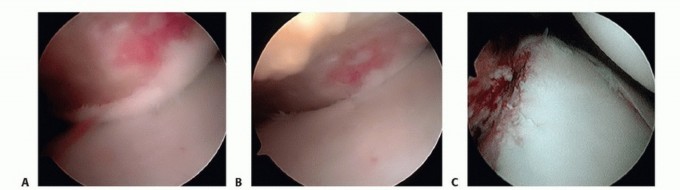

Diagnostic Arthroscopy and Portal Placement

We begin with a standard posterior viewing portal, established approximately 2 cm inferior and 1 cm medial to the posterolateral acromial angle. A thorough, systematic diagnostic sweep is performed. We meticulously document the integrity of the biceps anchor (assessing for SLAP tears), the articular surface of the rotator cuff, the bare area of the humeral head, and the entire 360-degree labral circumference. We specifically probe the anteroinferior labrum to assess the extent of the Bankart detachment and evaluate the volume and patulousness of the axillary pouch.

Image

The establishment of the anterior working portals is arguably the most critical step of the setup; poor portal placement condemns the surgeon to a difficult, compromised repair. Utilizing an outside-in spinal needle localization technique, an anterosuperior portal is created high in the rotator interval, just anterior to the biceps tendon. This serves primarily as a viewing portal for the inferior work and for suture management. The anteroinferior (5 o'clock) portal is then established just superior to the subscapularis tendon. This portal must be placed low enough to allow a 45-degree "deadman's angle" approach to the 5:30 position on the glenoid rim for the foundational inferior anchor.